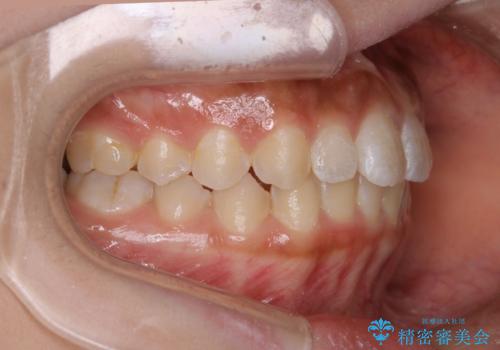

短期間ですきっ歯を改善:インビザラインLite

- 上の歯がすきっ歯なのと、歯が出ている気がするとご相談にいらした方です。

奥歯の噛み合わせに大きな問題がなく、患者様のご希望もあったため、前歯部メインで治療するインビザラインLiteで治療を行いました。

横顔のシルエットが改善し、口元もスッキリとなりました。